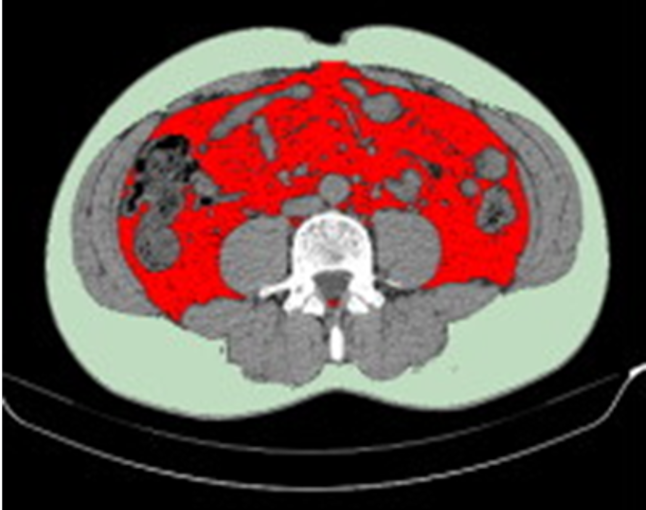

- 内臓脂肪を低減(図3、4)

- 男性の比較においては、金色のユーグレナ群は対照群と比較して、内臓脂肪面積の有意な低下が確認された(図3、4)。